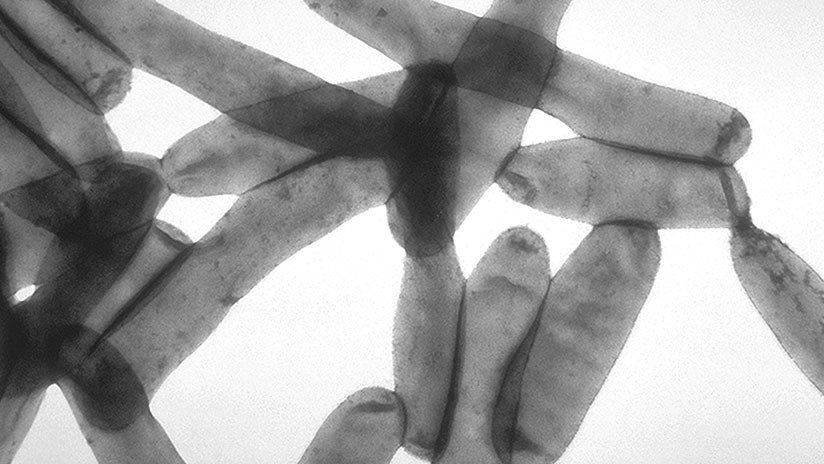

La bacteria Legionella fue detectada en varios puntos de la localidad mallorquina, pero tras analizar todas las muestras recogidas en los pacientes, los expertos notaron que todas ellas coincidían con aquella obtenida en uno de esos lugares.

- La legionelosis es una enfermedad infecciosa y potencialmente letal que afecta los pulmones.

- Esta afección no se transmite de una persona a otra, sino mediante el agua infectada proveniente de las torres de enfriamiento, sistemas de tubería, bañeras y duchas.